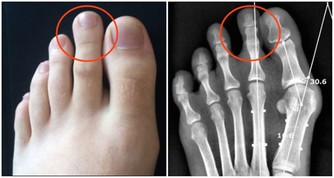

金瓜子油是維護男性前列腺健康最重要的一種食物。雙氫睾酮是前列腺增生的元兇,而金瓜子油中的植物甾醇類物質則可以阻止5α還原酶與睾酮發生化學反應產生雙氫睾酮,因此也就可以減少雙氫睾酮,從而使增生的前列腺組織萎縮。